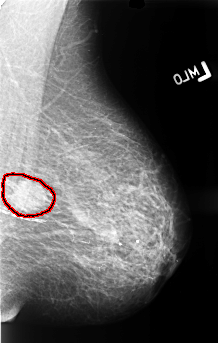

B_3413_1.LEFT_MLO

LEFT_MLO LINES 4448 PIXELS_PER_LINE 2832 BITS_PER_PIXEL 12 RESOLUTION 50 OVERLAY

FILE: B_3413_1.LEFT_MLO.OVERLAY

TOTAL_ABNORMALITIES 1

ABNORMALITY 1

LESION_TYPE CALCIFICATION TYPE N/A DISTRIBUTION CLUSTERED

LESION_TYPE MASS SHAPE IRREGULAR MARGINS ILL_DEFINED

ASSESSMENT 4

SUBTLETY 4

PATHOLOGY MALIGNANT

TOTAL_OUTLINES 1

BOUNDARY